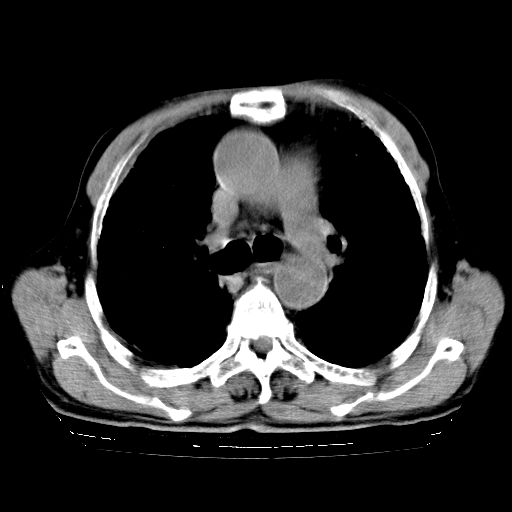

标题: CT25149:男,69岁,反复咳嗽、咳痰五年余,呼吸困难三天。 [打印本页]

男,69岁,反复咳嗽、咳痰五年余,呼吸困难三天。

慢支伴感染、肺气肿、肺心病

慢支伴感染、肺气肿、肺心病!支持!另:间质纤维化!

两肺间质性炎症并感染,左上叶肉芽肿

考虑慢性间质性肺炎并肺间质纤维化。

慢支伴感染、肺气肿、肺心病。双肺间质性改变(间质纤维化)。